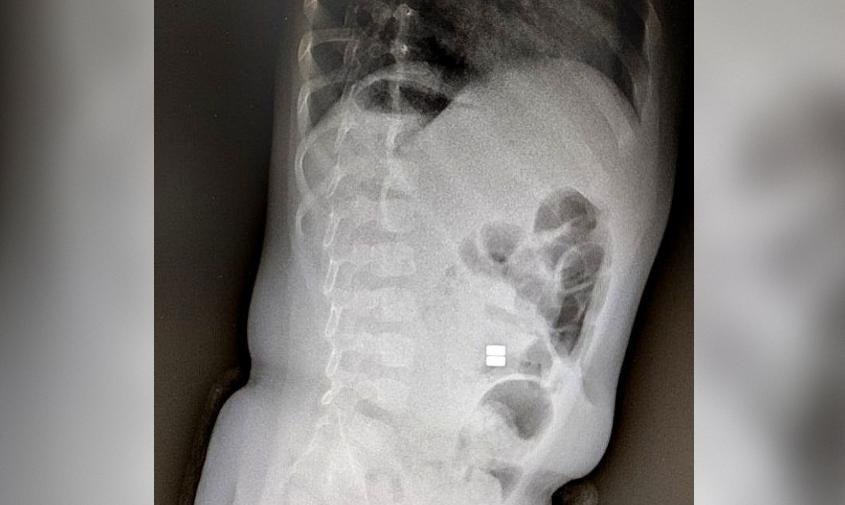

Амурские медики бьют тревогу: дети все чаще глотают магнитные шарики. В группе риска — малыши от полугода до трех лет. Врачи предупреждают: такие игрушки смертельно опасны.

Магниты слипаются внутри кишечника, сдавливают стенки, нарушают кровоснабжение. Последствия — перфорация, перитонит, непроходимость, иногда летальный исход. Оперировать сложно: чем больше шариков, тем больше повреждений, иногда нужны повторные вмешательства.

Фото: Минздрав Амурской области